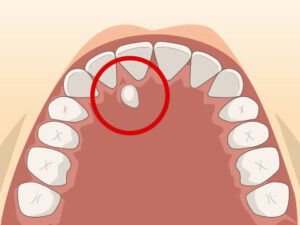

過剰歯ができやすい場所

特に多いのは、

- 上の前歯の真ん中

- 奥歯の後ろ

- 下あごの小臼歯部 です。

中でも有名なのが、上の前歯の間にできる

正中過剰歯(せいちゅうかじょうし)です。

この歯があると、

- 前歯が生えてこない

- 歯並びがずれる

- すきっ歯になる

- 隣の歯を押す ことがあります。